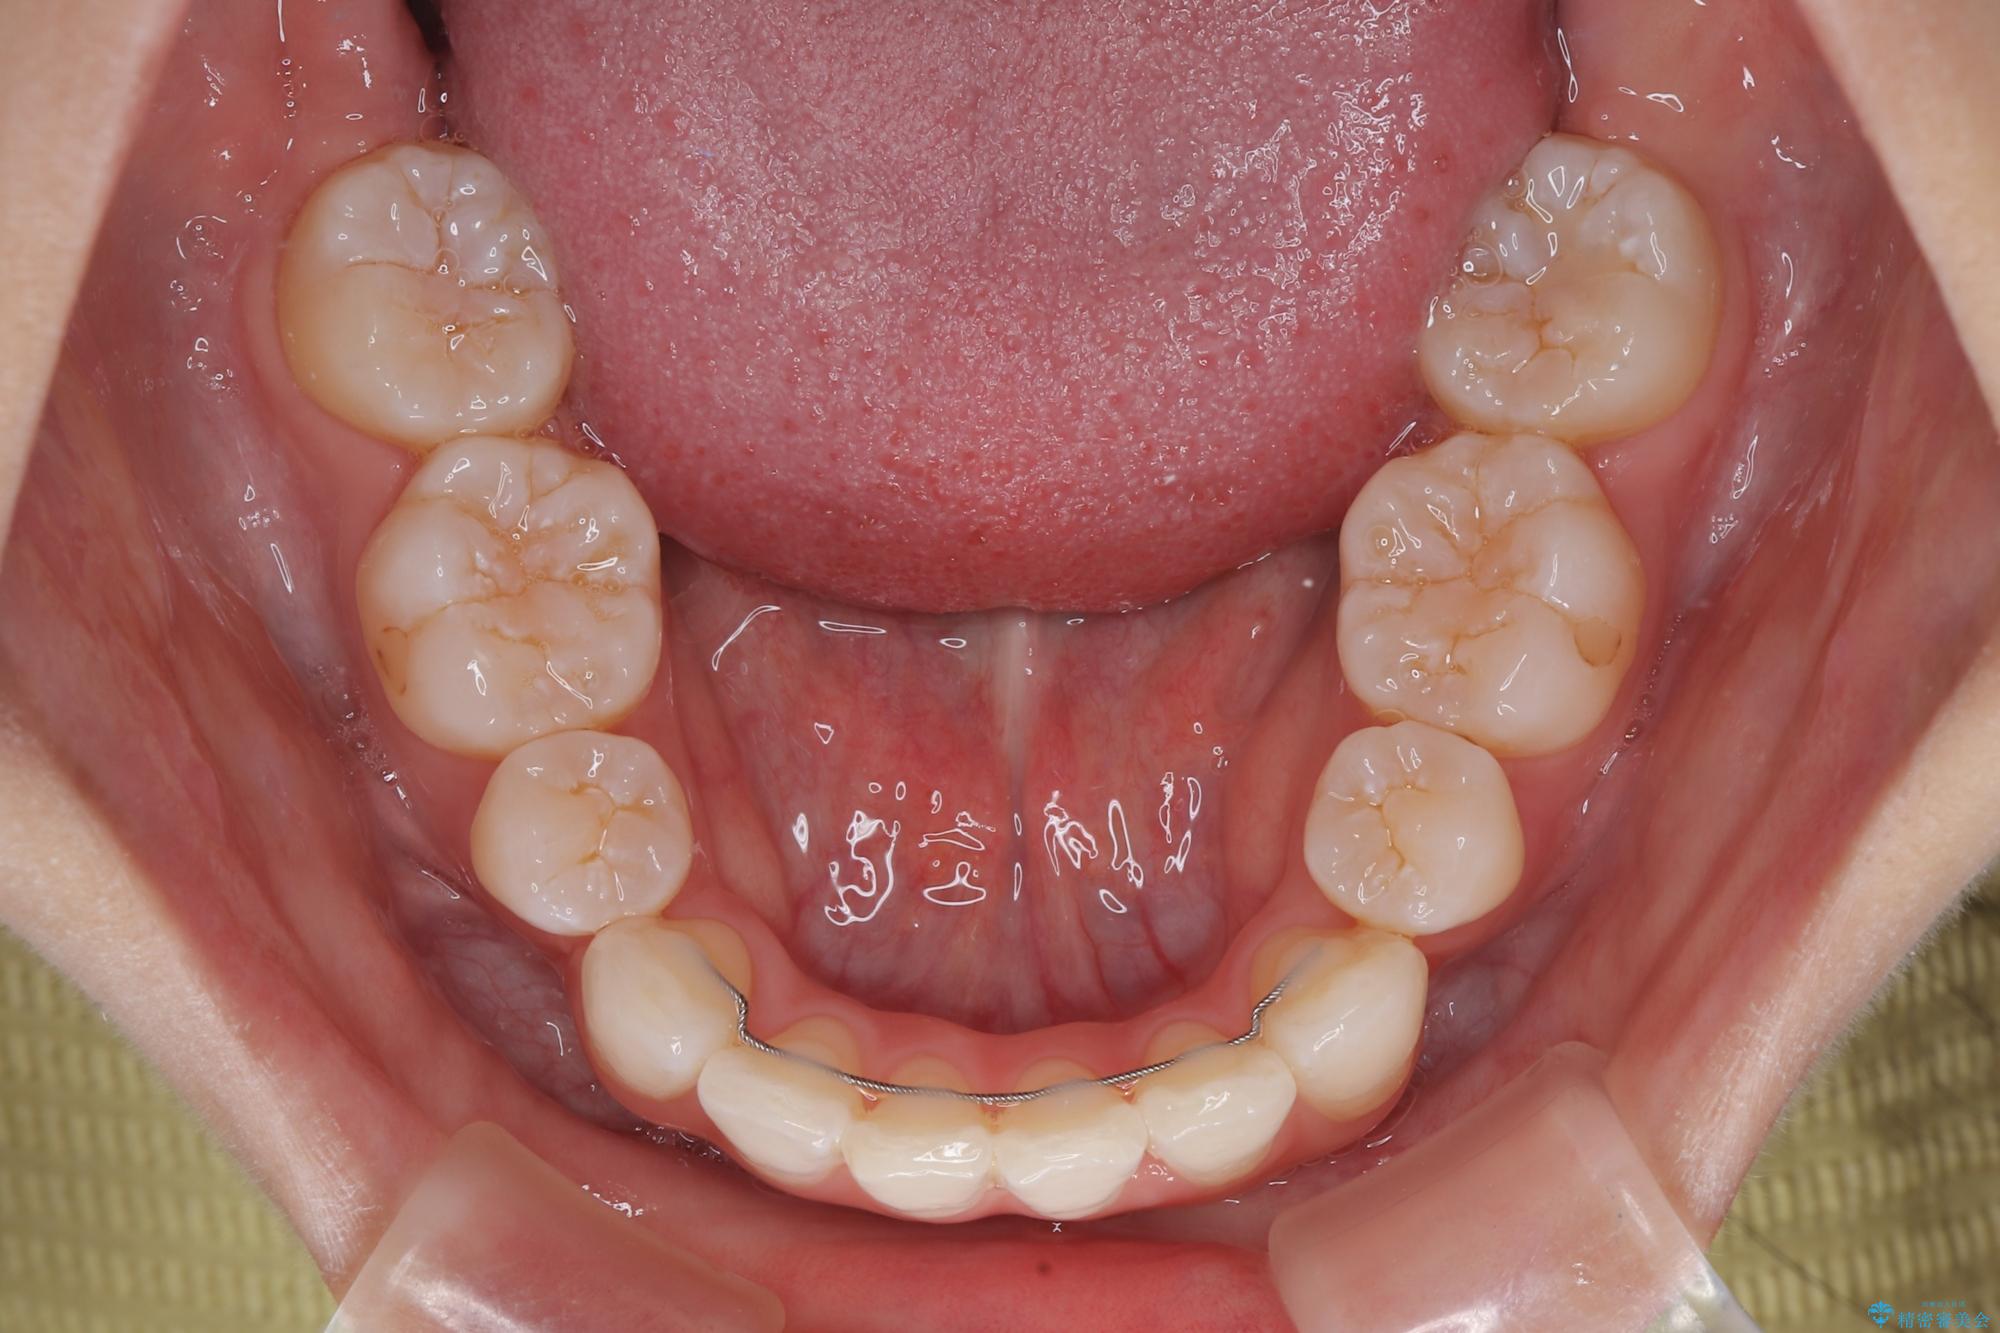

- 口を閉じたときに飛び出してしまう上顎前歯を気にして来院された患者様です。

下顎はデコボコが気になっていたため、上下左右第一小臼歯4本を抜去して、ワイヤー装置にて口元の突出感を改善するよう矯正治療を行うこととしました。

下唇に前歯が当たって跡が残ってしまう状態でしたが、スッキリとした口元に仕上げることができました。